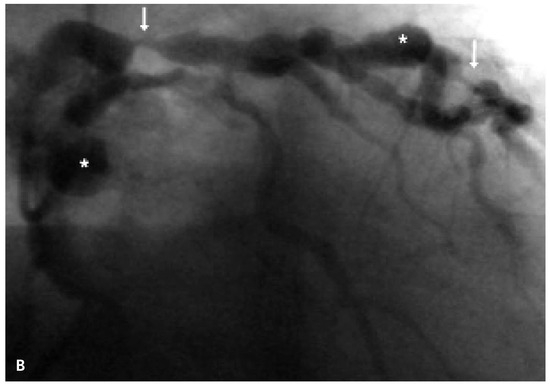

Fractional Flow Reserve in the Diagnosis of Ischemic Heart Disease in a Patient with Coronary Artery Ectasia

by Malgorzata Zalewska-Adamiec, Lukasz Kuzma, Hanna Bachorzewska-Gajewska and Slawomir Dobrzycki

Diagnostics 2022, 12(1), 17; https://doi.org/10.3390/diagnostics12010017 - 23 Dec 2021

Coronary artery ectasias (CAE) are diffuse dilatations of coronary artery segments with a diameter 1.5 times greater than the largest adjacent normal segment of the vessel. They are found in 0.3–5.0% of coronary angiography. Risk factors for CAE include atherosclerosis, previous percutaneous coronary [...] Read more.

Coronary artery ectasias (CAE) are diffuse dilatations of coronary artery segments with a diameter 1.5 times greater than the largest adjacent normal segment of the vessel. They are found in 0.3–5.0% of coronary angiography. Risk factors for CAE include atherosclerosis, previous percutaneous coronary interventions, arterial inflammation and connective tissue diseases. The diagnosis of CEA in a patient is a considerable diagnostic and therapeutic problem due to the unfavorable prognosis and the lack of guidelines. We present a case of a 69-year-old male patient with a history of retrosternal pain admitted to the clinic for the diagnosis of coronary artery disease. In coronary angiography, numerous ectases of the main coronary arteries and atherosclerotic lesions causing border stenosis of the left anterior descending (LAD), diagonal (2D) and marginal branch (OM). The heart team decided to assess the significance of the changes with the fractional flow reserve (FFR). The FFR was performed and haemodynamically insignificant stenoses of the ectatically dilated coronary arteries were found. The patient was qualified for conservative treatment. Full article